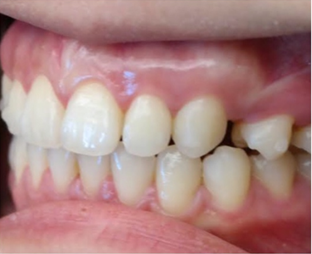

黄医生粗略的看了我的牙齿之后,说我存在两个问题,一个是开咬合(也就是后牙咬紧的时候上下牙之间还有差距),另一个是过咬合(后牙咬紧后上排牙比下排牙突出)。不夸张的说,那个前后差距我能放一根手指!

黄医生说我所有关于咬不开包装袋,嘴闭不上,睡觉呼吸方式,流口水,磨牙,右边咬肌突出,都是因为我的咬合完全不正确。过咬合和深咬合是很多亚洲人都有的问题,但是开咬合却不常见,要把我这“祖传”的嘴突治好,得靠改变我门牙和premolar的角度,然后整个上排往里推,牙齿的移动带着牙骨往里收,我的侧面会有很大的改善,我这种情况需要拔牙,但是智齿没有什么关系,一颗长出来了挺正,另外两颗深埋在牙床里离神经很近,取出来不但费很大功夫,还要冒脸瘫的风险,对我实际上没有任何影响。

有图有真相

3.15是我安装牙套的第一天,到10.16号已经整整七个月了,不管是牙齿上的改变,和脸部的改变都还蛮大的,许久不见我的朋友都会觉得我变了个人,也很多人说我脸瘦了,其实人家不是胖啦,只是肉很多!不多说,上图

其实还有20个牙套,但是我的凸牙已经基本上都回去了,改变巨大。下面放羞羞的真人图。

2017.03.15

2017.08.02

2017.10.17

比较明显的是我的人中明显变长,嘴突有了很大改善,下巴也因此显得更长,我发现最惊喜的改变是,我的肉肉脸!!!没有了!!!